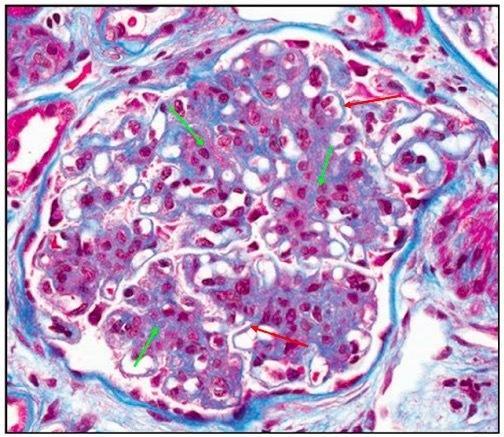

图 26 Masson 染色 绿色箭头:肾小球系膜区基质增多,且呈红色,不同于其它病变的蓝色;红色箭头:毛细血管内细胞增生